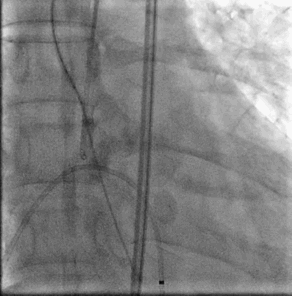

结合术前CT判断和术中影像判断,最终决定植入L26号venus A瓣膜。采取标准位置释放。

一开始可以将ring释放到mark点往下2mm处,暂停释放张力,造影观察位置,此时仍可以轻松上下调整

继续释放支架开始贴壁,此时血压还没完成下降,支架仍未完全开花

可以进行造影,观察位置

继续释放支架此时支架开花,血压下降到60以下时,可进行120-140起搏释放

建议此时释放速度无需过快,以便第一术者有间隙调整瓣膜位置,第三术者固定导丝

释放到血压开始回升停起博,造影,拉回辅路猪尾

继续释放完瓣膜,注意三个T头脱勾后撤出输送系统,交换猪尾到心室,进行根部造影